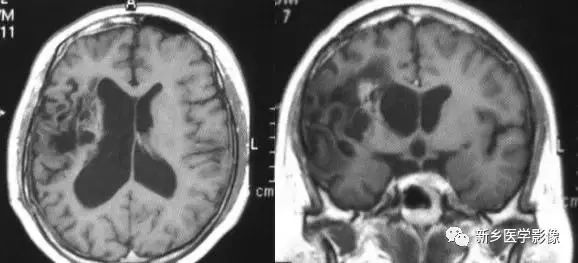

❷ 一侧大脑半球萎缩

可由许多原因引起,如脑梗死、外伤、出血及感染等。最常见的原因是血管闭塞引起大面积脑梗死。CT和MRI表现为:患侧侧脑室扩大、脑组织量减少,中线向患侧移位,严重者脑沟和脑回消失不见。

❸ 脑三叉神经血管瘤病

又称为脑-颜面血管瘤综合征。CT平扫以一侧半球脑实质内脑回样、轨道样、弧带状或锯齿状钙化为特征。由于受累侧血供障碍,常引起脑实质萎缩。所以可以表现有:患侧侧脑室扩大、颅腔变小、颅板增厚。特征是脑内可见典型钙化及临床三叉神经分布区有紫红色血管痣。